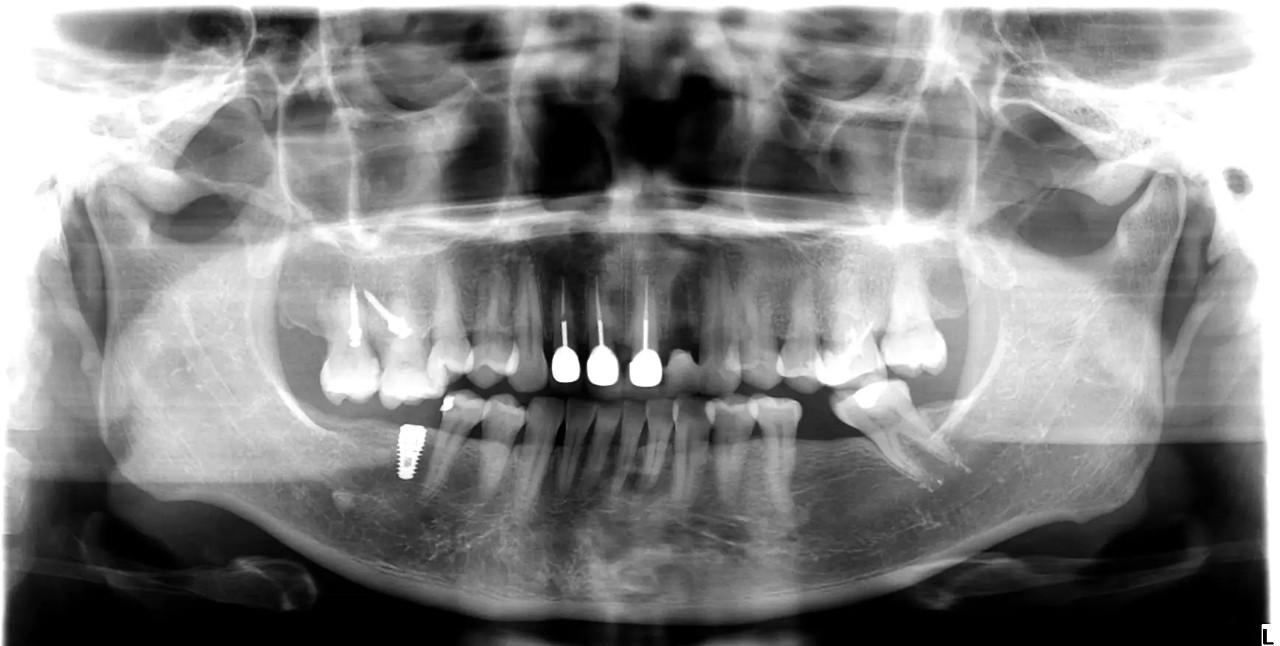

Teo xương hàm : Khi mất răng, xương hàm không còn được kích thích bởi các lực nhai, dẫn đến việc mất dần chất lượng và khối lượng xương tại khu vực mất răng. Điều này có thể làm thay đổi khuôn mặt và làm giảm khả năng lắp răng giả hoặc cấy ghép sau này.

Cấy ghép răng (Implant) : Đây là phương pháp phổ biến và hiệu quả nhất để phục hồi răng đã mất. Cấy ghép răng giúp phục hồi chức năng nhai và ngăn ngừa tình trạng teo xương hàm. Cấy ghép được cấy vào xương hàm và có thể lắp răng giả lên đó.